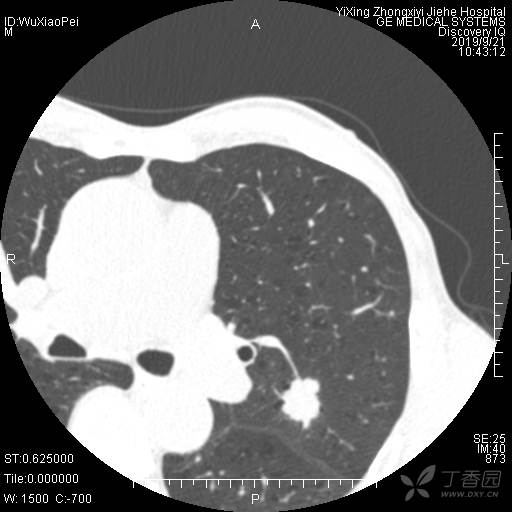

简要病史:咳嗽伴左腰痛一周。体检发现左上肺占位。

辅助检查:外院CT提示:左上肺占位,肺气肿;超声提示:甲状腺小结节

临床诊断:右上肺占位(性质待查)

治疗经过:手术切除